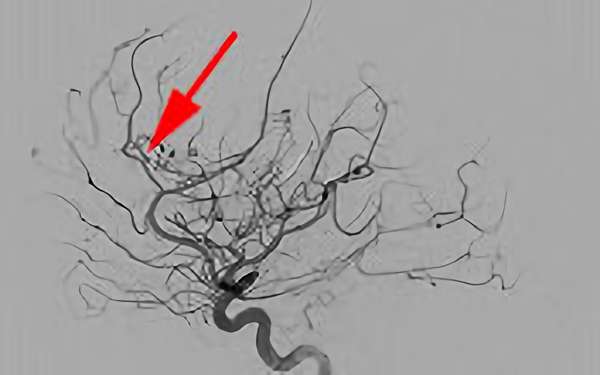

No.1482 手術中

No.1442 手術中

No.1391 手術中

No.1361 手術中

No.1283 手術中

No.1263 手術中

No.1173 手術中

No.1112 手術中

No.1018 手術中

No.847 手術中

No.835 手術中

No.803 手術中

No.775 手術中

No.664 手術中

No.642 手術中

No.623 手術中

No.622 手術中

No.586 手術中

No.585 手術中

No.569 手術中

No.568 手術中

No.550 手術中

No.547 手術中

No.546 手術中

No.524 手術中

No.498 手術中

No.481 手術中

No.480 手術中

No.470 手術中

No.401 手術中

No.387 手術中

No.316 手術中

No.308 手術中

No.299 手術中

No.246 手術中

No.245 手術中

No.224 手術中

No.206 手術中

No.162 手術中

No.133 手術中

No.99 手術中

No.98 手術中

No.94 手術中

No.62 手術中

No.37 手術中

No.24 手術中

No.17 手術中

No.9 手術中